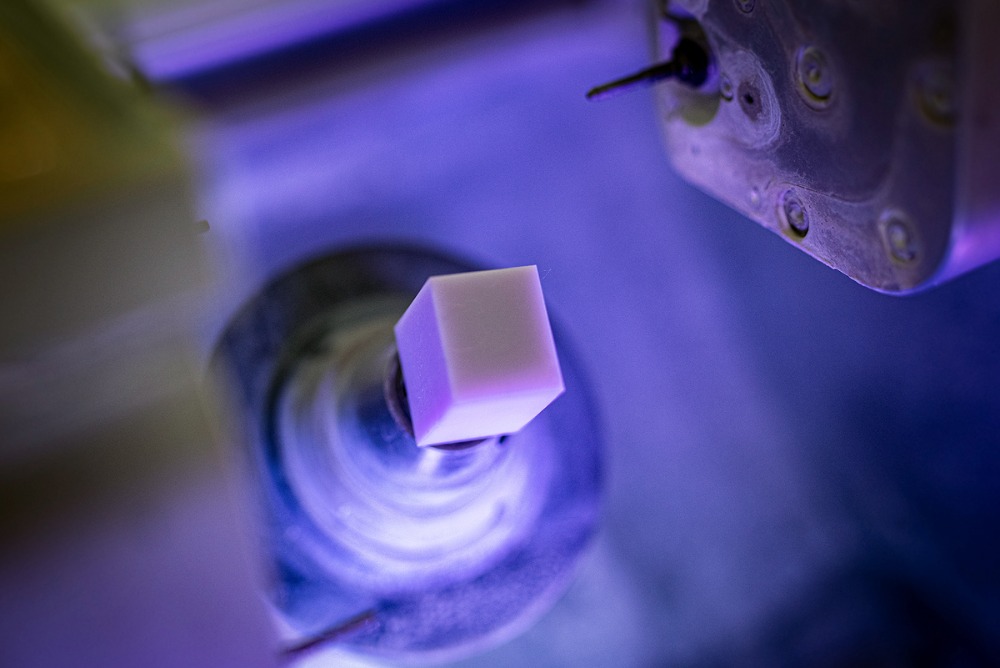

Výroba estetických celokeramických korunek dle sceneru, individuálně pro každého jednotlivého pacienta, dle vzhledu, fyziognomie obličeje a genetiky zubů.